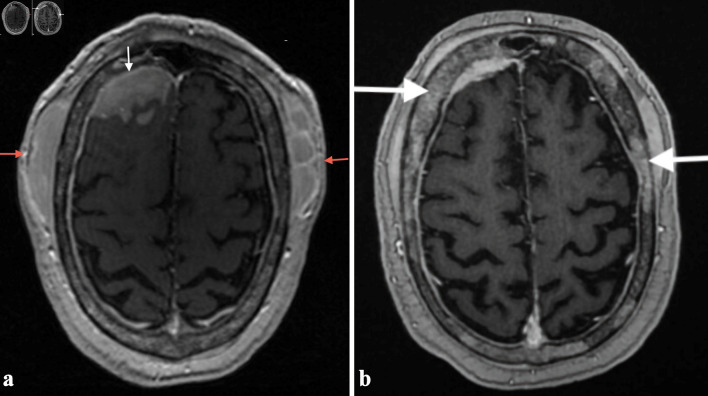

外周T细胞淋巴瘤(PTCL-NOS)是一种罕见的侵袭性非霍奇金淋巴瘤(NHL)亚型,起源于成熟的T细胞或自然杀伤细胞(NK),约占所有NHL病例的5%。虽然PTCL-NOS通常累及淋巴结,但结外部位如皮肤、胃肠道、肝脏和肺部也可能受到影响。中枢神经系统(CNS)受累是极其罕见的,特别是在最初的表现。当它确实发生时,最常受影响的是大脑,其次是脊髓和脑膜。我们报告一例罕见的PTCL-NOS合并继发性中枢神经系统淋巴瘤累及脑膜的病例。我们的病人是一名75岁的男性,患有多种合并症,表现为几周的间歇性头痛。影像学显示多发性轴外脑病变,浸润到颅外软组织、硬膜外间隙、脑膜和脑实质。随后的淋巴结活检证实PTCL-NOS。他开始使用利妥昔单抗、环磷酰胺、阿霉素、长春新碱和强的松(R-CHOP),并计划使用大剂量甲氨蝶呤。此后,患者因各种并发症多次再次入院,并在诊断后约2.5个月死亡。我们得出结论,PTCL-NOS继发性中枢神经系统受累非常罕见,预后较差,中枢神经系统诊断后的中位生存期约为1.1个月。早期诊断和量身定制的治疗策略,包括中枢神经系统穿透剂,是必不可少的。需要继续研究以更好地了解和改善这种侵袭性疾病的结果。

Peripheral T-cell lymphoma, not otherwise specified (PTCL-NOS), is a rare and aggressive subtype of non-Hodgkin lymphoma (NHL) that arises from mature T or natural killer (NK) cells, accounting for about 5% of all NHL cases. While PTCL-NOS typically involves lymph nodes, extranodal sites such as the skin, gastrointestinal tract, liver, and lungs can also be affected. Central nervous system (CNS) involvement is extremely rare, especially at the time of initial presentation. When it does occur, the brain is most commonly affected, followed by the spinal cord and meninges. We present a rare case of PTCL-NOS with secondary CNS lymphoma involving the meninges at initial diagnosis. Our patient is a 75-year-old male with multiple comorbidities who presented with several weeks of intermittent headaches. Imaging showed multiple extra-axial brain lesions with infiltration into extracranial soft tissues, epidural space, meninges, and brain parenchyma. A subsequent lymph node biopsy confirmed PTCL-NOS. He was started on rituximab, cyclophosphamide, doxorubicin, vincristine, and prednisone (R-CHOP), with plans for high-dose methotrexate. Thereafter, the patient was readmitted several times due to various complications and expired approximately 2.5 months after diagnosis. We conclude that secondary CNS involvement in PTCL-NOS is very rare and has a poor prognosis, with a median survival after CNS diagnosis of about 1.1 months. Early diagnosis and tailored treatment strategies, including CNS-penetrating agents, are essential. Continued research is needed to better understand and improve outcomes for this aggressive disease.